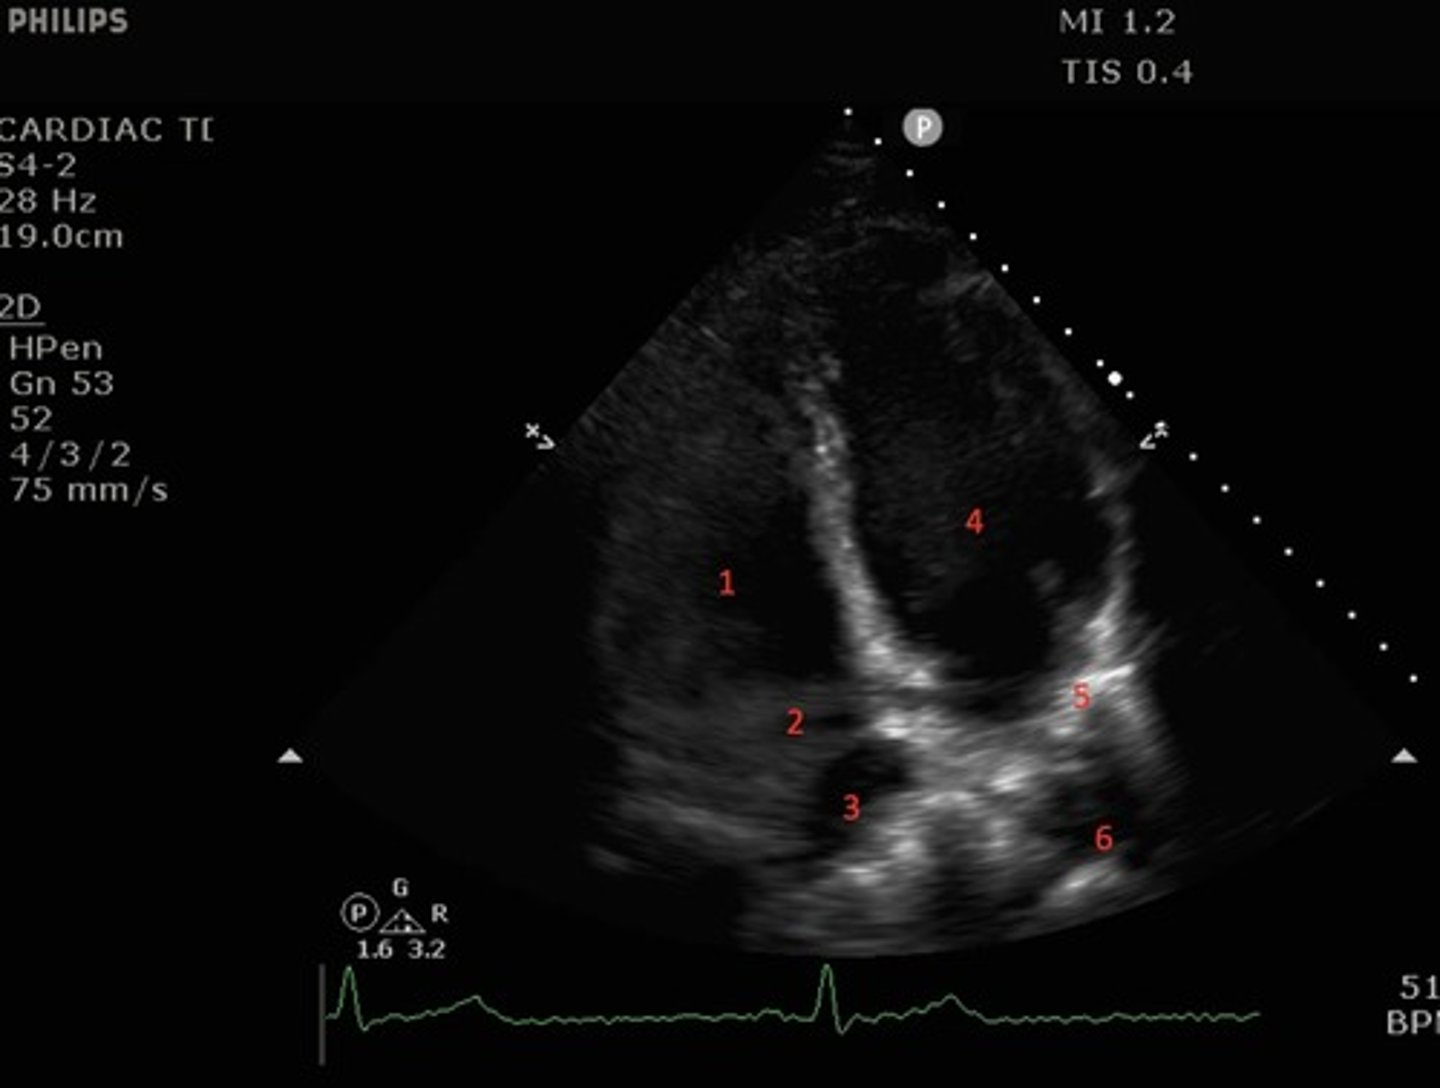

Parasternal long axis

What view of the heart is this?

1. right atrium

2.tricuspid valve

3.right ventricle

4. pulmonic valve

5.pulmonary artery

6. left atrium

red circle: aortic valve

identify the numbered and circled structures

what structures are seen with parasternal long axis view?